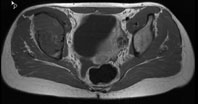

Ein 13-jähriges Mädchen kommt humpelnd zu Ihnen in die Praxis mit Schmerzen in der rechten Hüfte, die seit einigen Monaten bestehen und besonders bei Belastungen auftreten. Eine sichtbare Schwellung besteht nicht, kein Sturzgeschehen in der Anamnese.

Die Röntgenuntersuchung von Becken/Hüfte zeigt eine septierte geographische Osteolyse in der Ala und im Korpus des Os Iliums rechts. Das Röntgenbild und die Aufnahmen der nachfolgenden MRI-Untersuchung sehen Sie hier:

T2 FS, axial, 5 mm

Bild vergrössern